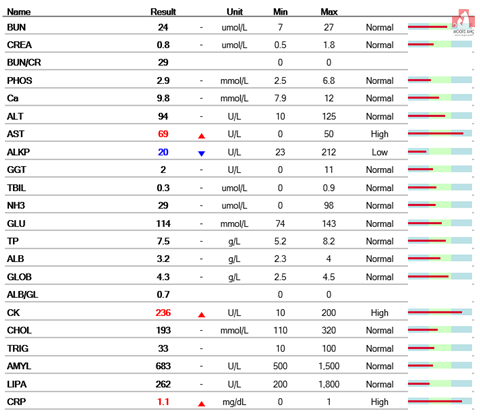

먼저 마취전 검사를 하기로 했어요.

다행히 혈액검사상으로는 탈장에 의한 근 손상으로 AST, CK가 올라간 것 이외의 특이 소견은 없었습니다.

그러나 혈액 검사 상 신장의 수치는 양호하고 마취에 관해서는 괜찮다고 생각됩니다.